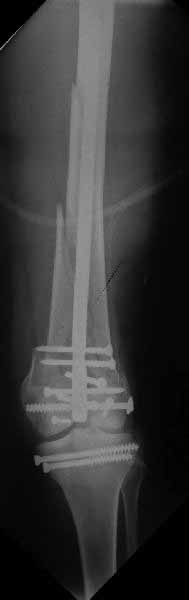

Ответ на эту часть Вашего поста – вложенный файл. Больная оперирована неделю назад по поводу открытого перелома дистального эпиметафиза бедренной кости. После операции она идёт в рентгенкабинет для выполнения послеоперационной контрольной рентгенографии, представленной на слайдах 10 и 11. Узнав, почему её фотографируют, просила передать Вам, Антон, привет.

И уже лет шесть мы используем возможность ввести в дистальное овальное отверстие 3 винта, которые именно запираются в этом отверстии, не люфтят, а обеспечивают угловую стабильность - см картинку.

Получается и стабильно, и очень дистально, нижний край отверстия в 3 мм от дистального конца гвоздя.